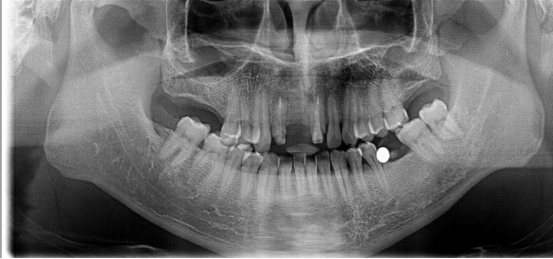

全口種植牙修復案例

病例簡介:

郭先生今年67歲,是位白手起家的成功企業(yè)家。早期忙碌的工作讓他疏于口腔保健,導致他上下牙列缺失。郭先生表示在二十年前在國外已經做過種植牙,但是近期來我院就診時其之前種植牙的種植體已經滑入到上頜竇內。

“患者前牙骨量不足,壁薄,后牙因手術取出以前的種植體導致了骨頭的大量缺損,所以需要植骨才能進行種植牙手術。種植需要避開手術后的骨缺失區(qū),所以對種植體的承受力和穩(wěn)定性要求較高,同時患者對美觀要求較高?!眲⒈笤淌谠诹私饬嘶颊叩男枨笈c口腔情況后為他進行了植骨手術,傷口愈合后,劉斌元教授為他進行CT掃描后確認可以進行種植牙手術。

手術成功結束,郭先生的全口牙齒全部種上,郭先生表示種牙后感覺很好,使用起來很方便:“終于吃上了我喜歡的堅果了!”